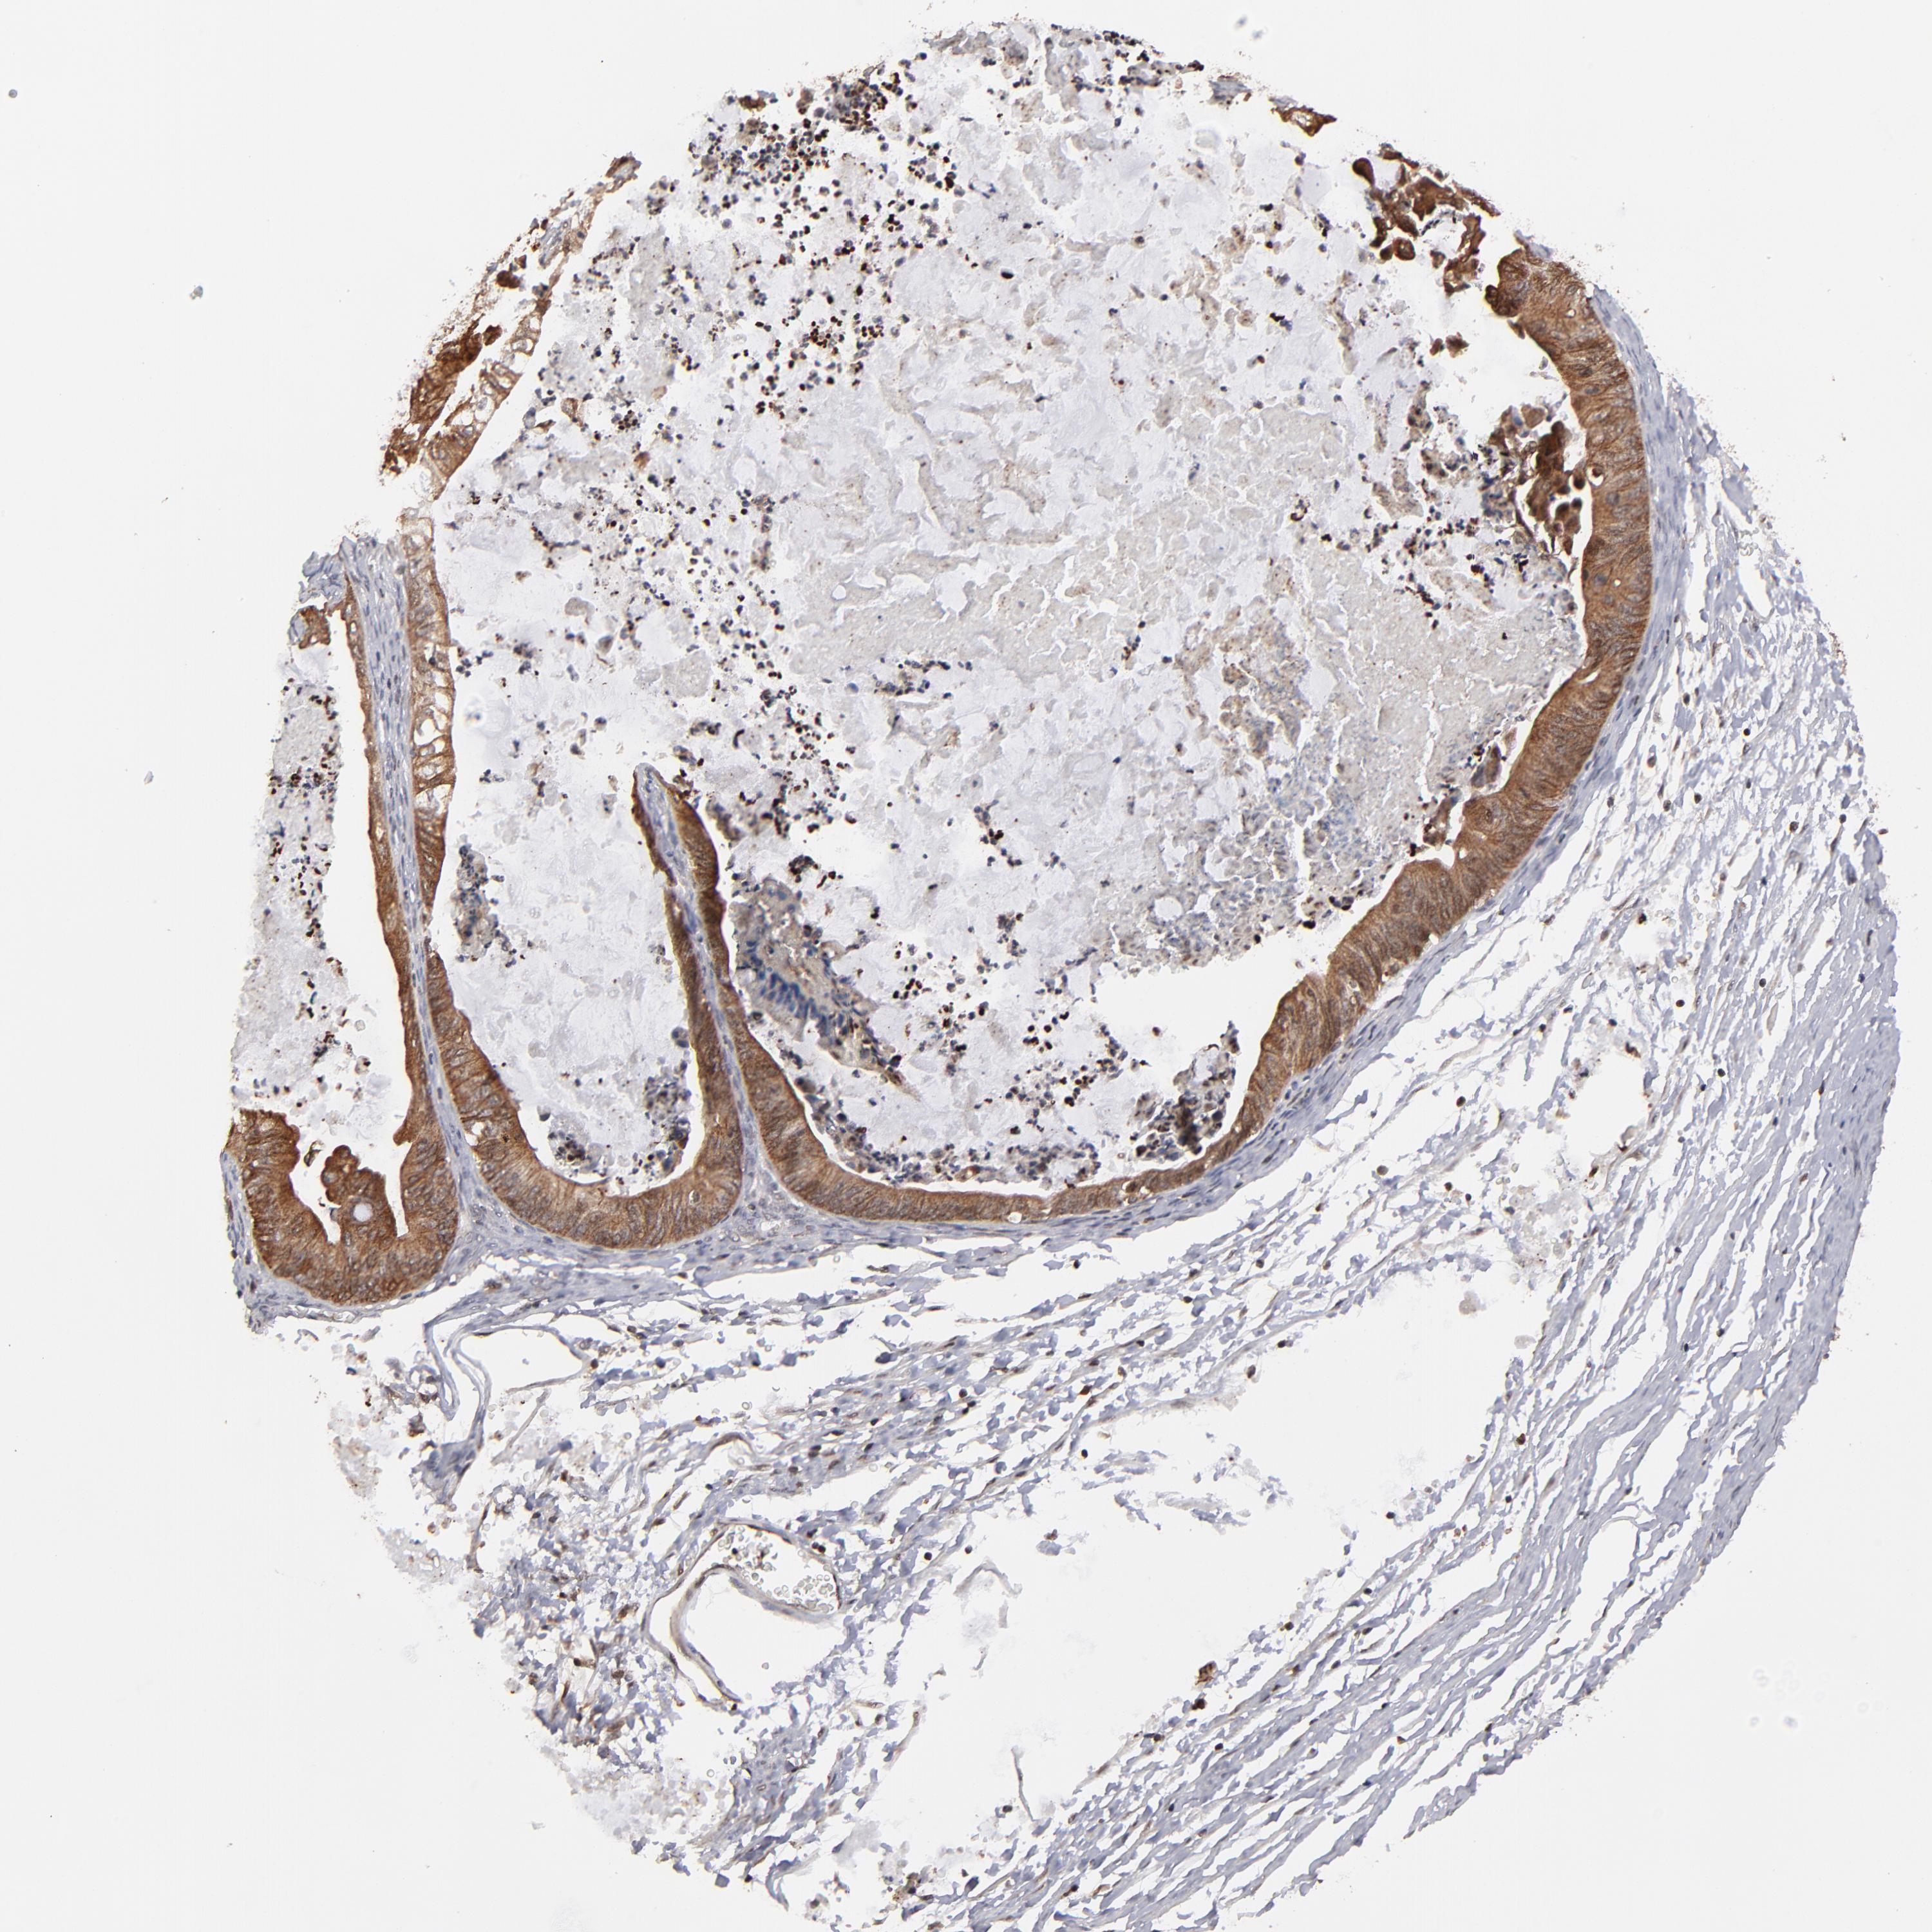

OVARIAN CANCER - Protein expressioni

A mouse-over function shows sample information and annotation data. Click on an image to view it in a full screen mode. Samples can be filtered based on level of antibody staining by selecting one or several of the following categories: high, medium, low and not detected. The assay and annotation is described here.

Note that samples used for immunohistochemistry by the Human Protein Atlas do not correspond to samples in the TCGA dataset.

Antibody stainingi

Antibody staining in the annotated cell types in the current human tissue is reported as not detected, low, medium, or high, based on conventional immunohistochemistry profiling in selected tissues. This score is based on the combination of the staining intensity and fraction of stained cells.

Each image is clickable and will lead to virtual microscopy that enables deeper exploration of all samples and also displays staining intensity scores, fraction scores and subcellular localization as well as patient and tissue information for each sample.

Antibody HPA003067

Staining

High

Medium

Low

Not detected

Intensity

Strong

Moderate

Weak

Negative

Quantity

>75%

75%-25%

<25%

None

Location

Nuclear

Cytoplasmic/membranous

Cytoplasmic/membranous,nuclear

Cystadenocarcinoma, serous, NOS

Cystadenocarcinoma, mucinous, NOS

Carcinoma, endometroid